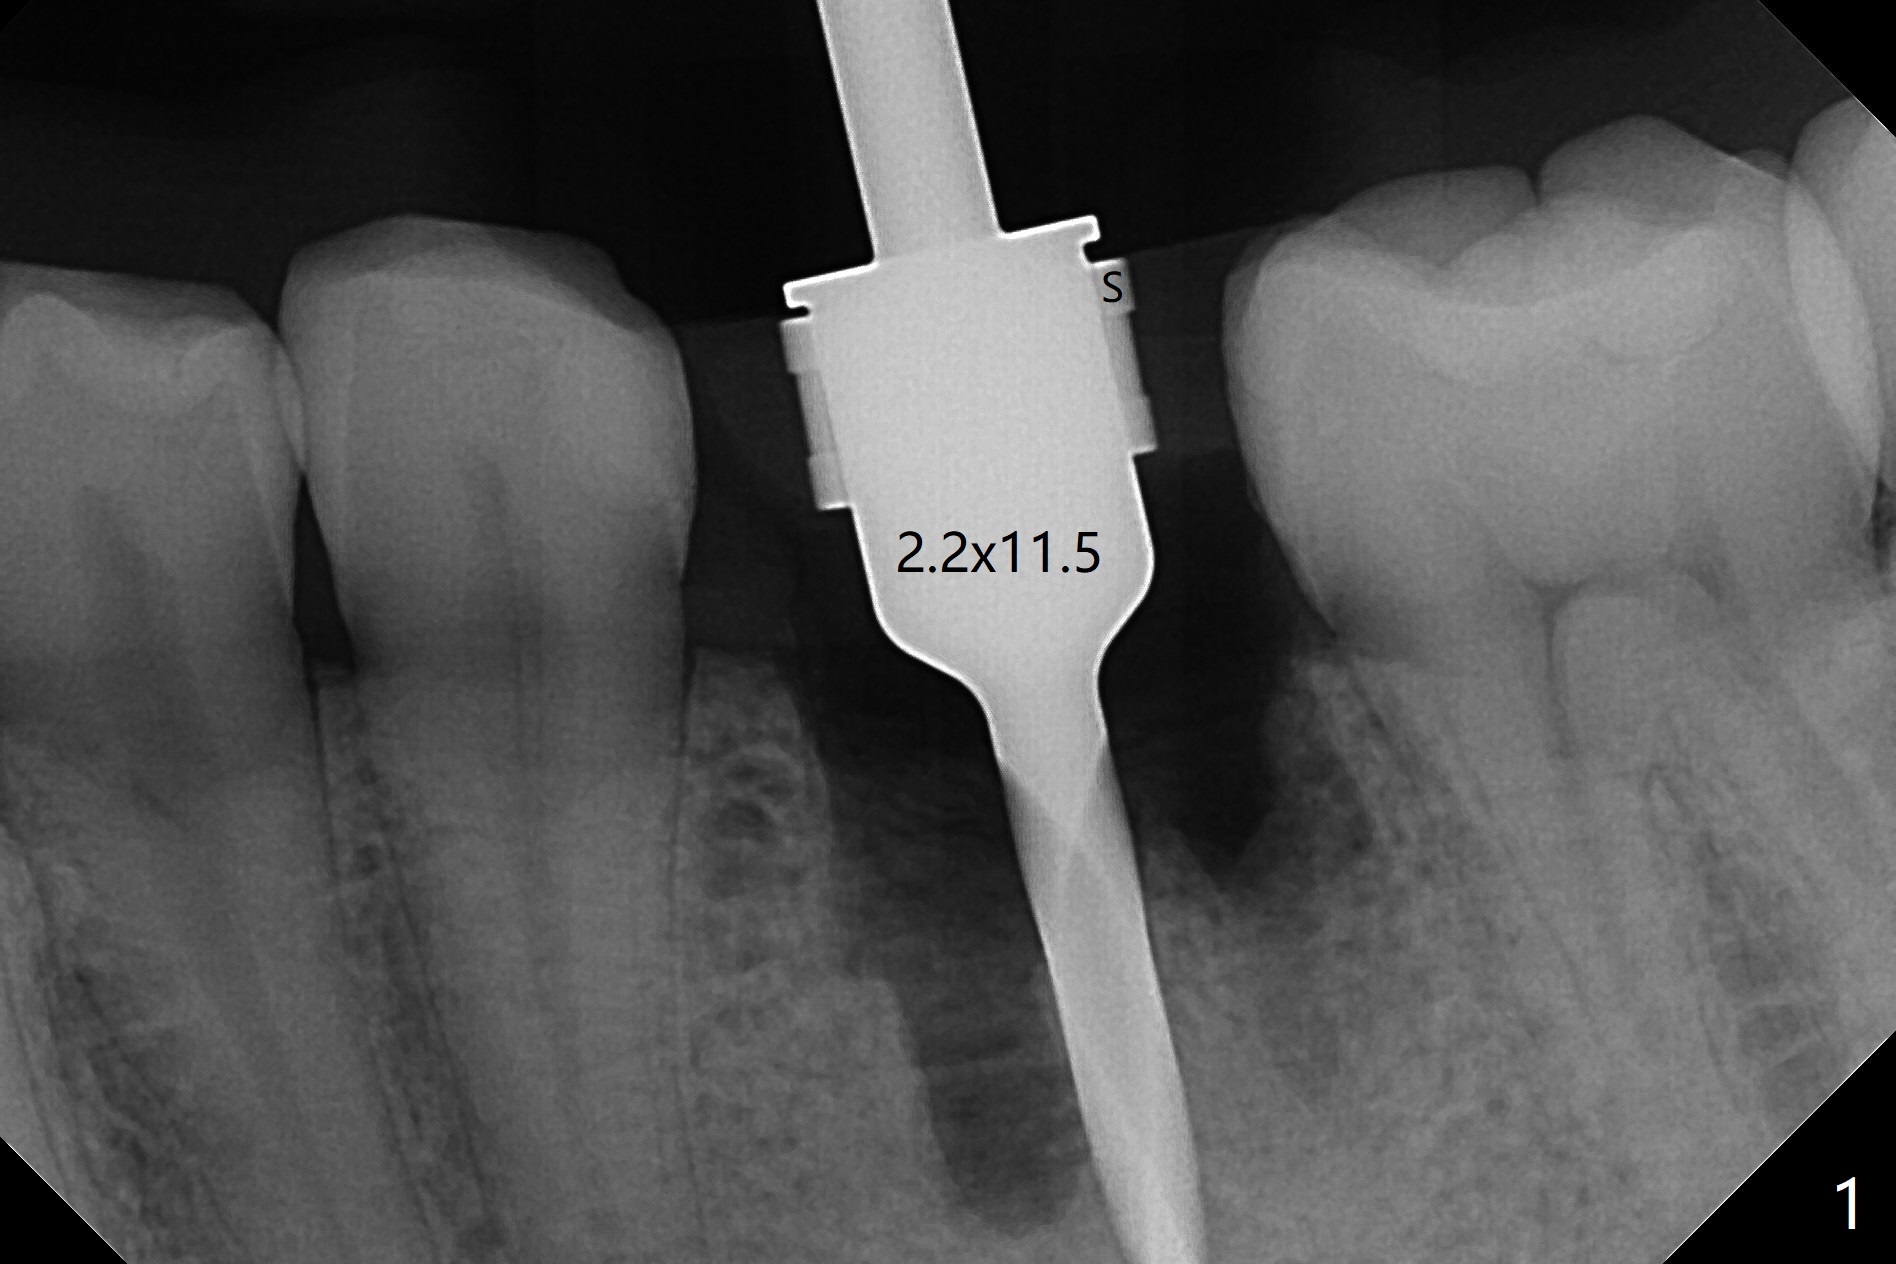

54岁男左下6根管治疗不成功,远中舌侧根弯曲,拔除时牙齿牙根多次断裂,骨质也硬,即使使用2.2毫米钻头也很吃力,钻至11.5毫米深,拍摄根尖片,显示钻洞没有明显偏移(图一),临床观察一致。当钻头直径增大,浅部钻洞,震动大,深部时,震动慢慢减少。为了植入5x11毫米植体,钻头必须4.5毫米,植体还必须反复倒旋转,才能减少扭力至40Ncm。由于没有骨质阻挡,基台放置尚顺利(图二)。拔牙时舌侧远中骨壁破坏,植入粘性骨粉重点放入 (图三:*),表面覆盖一张PRF膜(图四),最后制作临时牙冠。术后1.5月调整临时牙冠,牙槽窝愈合正常(图五)。